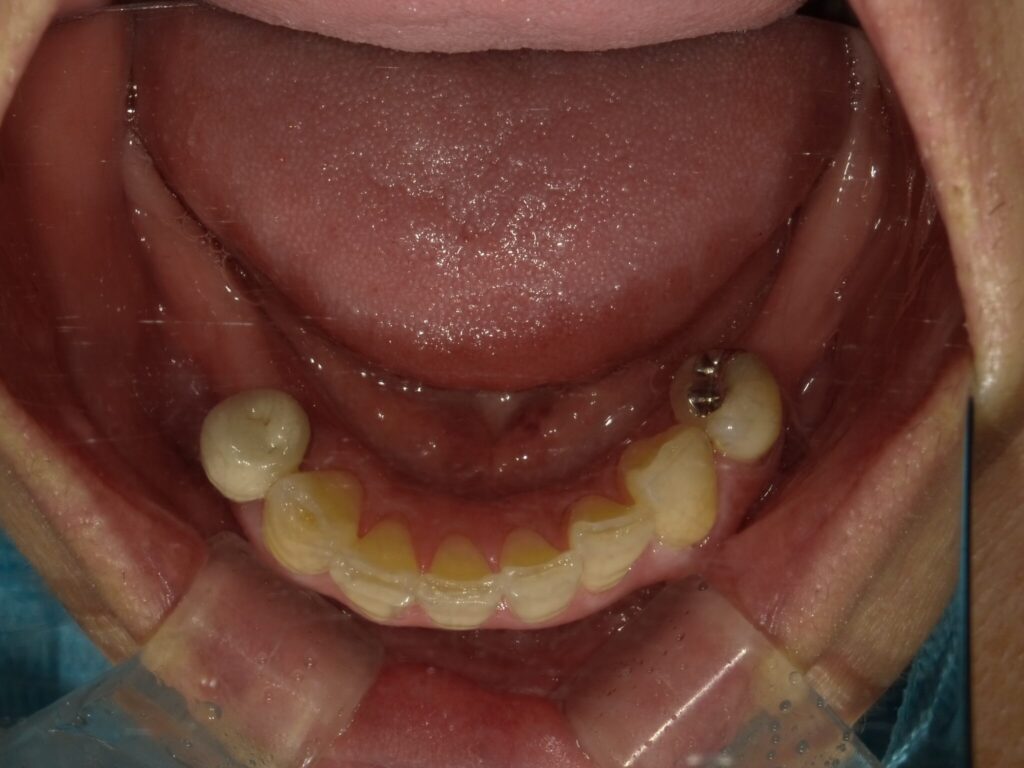

全顎治療症例

| 主訴 | 全体的に見た目を綺麗にしたい。奥歯でしっかり噛みたい。 |

| 診断名・ 主な症状 |

臼歯部欠損 |

| 治療内容 | インプラント埋入(左下5・6,右下5・6,左上4・6) サイナスリフト(左上4・6) ジルコニアBr(右上6−左上3) E –MAX CAD(右下4) セラミックインレー(左下4) |